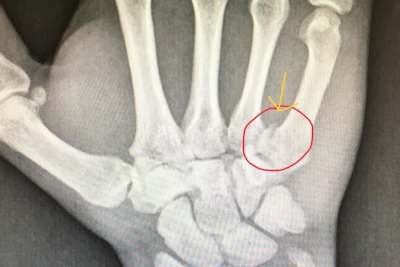

Im Zeittraining zum WM-Lauf hatte es geregnet und Vincon liess es nicht übertrieben schnell angehen. Doch das Sondieren der Streckenverhältnisse ging gerade mal zwei Runden lang. Das Hinterrad ging weg und er flog per Highsider ab. "Der Sturz selber war jetzt nicht so schlimm", erklärt er. "Aber ich bin halt blöd auf die rechte Hand gefallen." Zeit für einen Arztbesuch blieb nicht. "Es war ja Quali", so die einfache Antwort nach dem Warum. "Im Nassen ging es noch ganz gut, als die Strecke abtrocknete war mir schon klar, dass es problematisch werden würde. Meine Zeiten waren nicht hervorragend aber akzeptabel." Der Arztbesuch Anfang dieser Woche brachte dann den Bruch des fünften Mittelhandknochens zu Tage. Ein Bruch, der ohne Operation ca. sechs Wochen zur Heilung benötigt. Zu lang für Dominik Vincon. Er unterzog sich einer ambulanten Operation. "Es wurde dann doch etwas größer", erzählt er. "Aber viel hält viel. Ich will ja in drei Wochen beim Endurance-Finale in Oschersleben dabei sein."